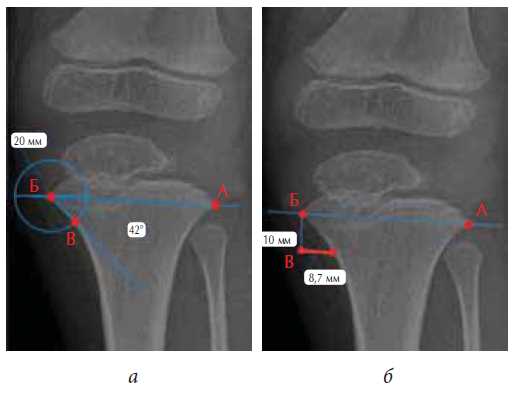

The AEJ was constructed by drawing a straight line through the maximally protruding points of the proximal metaphysis of the tibia bone and the distal metaphysis of the femoral bone (A and B). A circle was then drawn with the center at point A or B, depending on the zone of interest, with a radius of 10 mm (diameter 20 mm). At the intersection of this circle with the metaphysis of the bone, point C was determined. Points A (B) and C were connected by a straight line, and the value of the ABC angle (the AEJ) was determined (Fig. 1a).

Fig. 1. Schemes of calculation of the proposed indicators on the radiographs of the knee in a direct projection: a - calculation of the angle of the epimetaphyseal transition; b - calculation of the epimetaphyseal transition index

The IEJ was calculated by drawing a straight line through the maximum protruding points of the metaphysis (A and B) of the bones. A 10-mm-long straight line was then drawn perpendicular to the AB line through point B or A, depending on the zone of interest (point C). A straight line was drawn perpendicular to the BC line through point C to the bone metaphysis. Point D was placed at the intersection of this line with the bone metaphysis. The CD distance was measured (Fig. 1b). The 10 mm distance used in the calculation was to account for the special design of the plates, as the remoteness of the screw holes in the plate from its center is 10 mm. Thus, the position of the metaphyseal screw could be predicted at a distance of 10 mm from the growth zone with a high degree of accuracy.